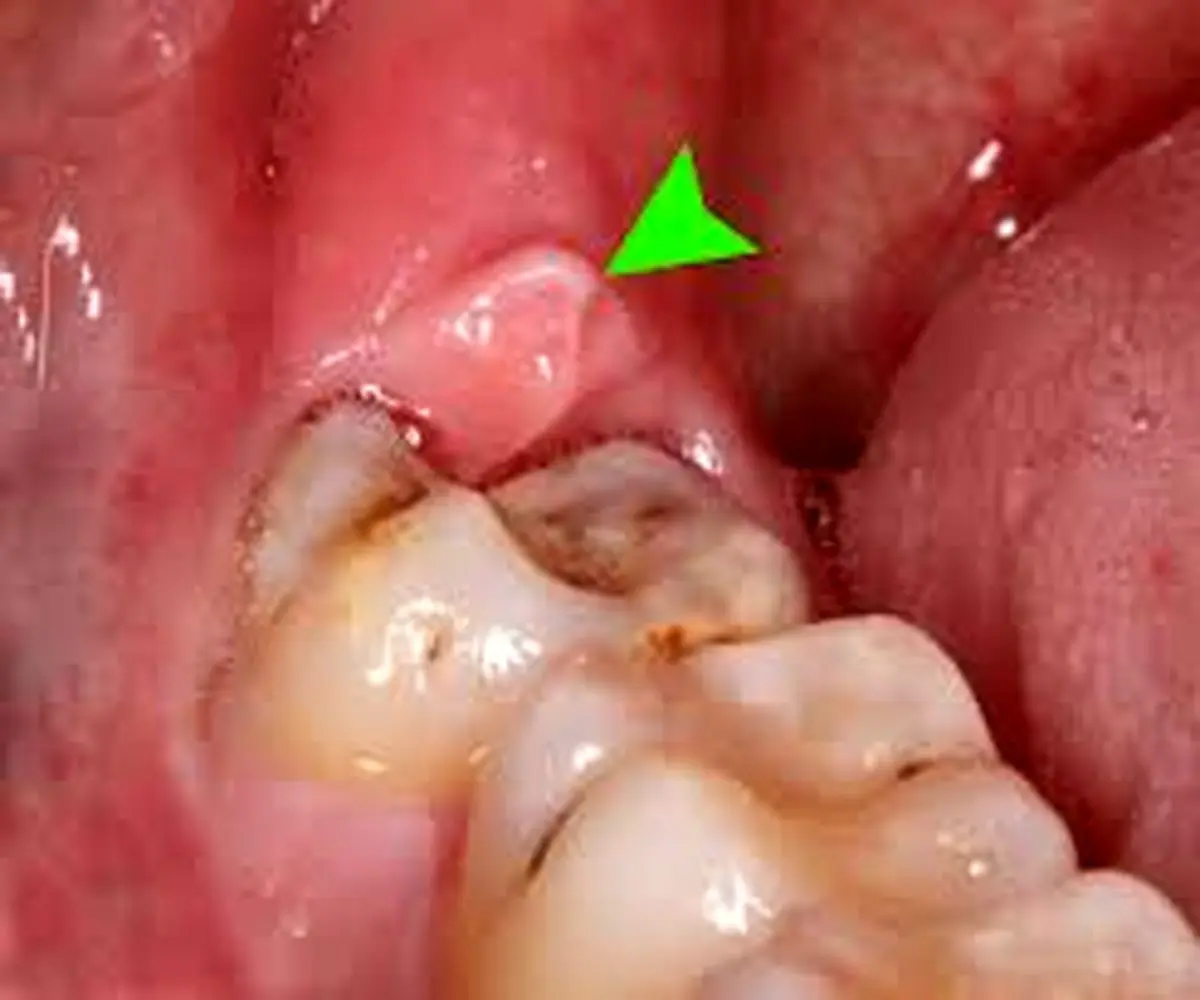

وی با بیان اینکه گاه به دلایلی مانند ارث، بیماری‌های دوران کودکی، کم خونی و راشیتیسم یعنی عدم هماهنگی رشد استخوان فک با اندازه دندان‌ها، این دندان‌ها در داخل فک، نهفته می‌مانند؛ گفت: اگر قسمتی از تاج آن‌ها به طور ناقص در دهان ظاهر ‌شود، در این صورت به آن دندان عقل، نیمه نهفته گفته می‌شود.

وی با اشاره به اینکه چنین دندان عقلی، ممکن است در بافت نرم یا سخت گیر کرده باشد، تصریح کرد: التهاب بافت نرم پوشاننده این دندان‌ها در اغلب موارد در ارتباط با دندان‌های نیمه رویش یافته اتفاق می‌افتد. پوسیدگی دندان عقل یا پوسیدگی دندان مجاور آن، از جمله مشکلاتی است که دندان‌های نهفته عقل می‌توانند ایجاد کنند.